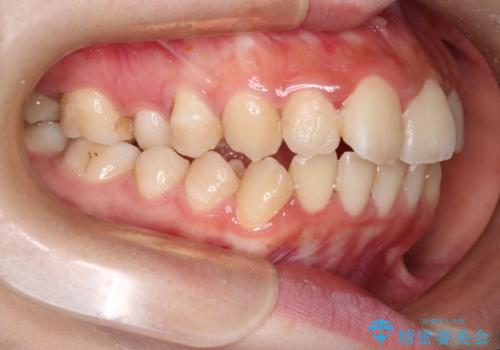

- 口元が出ていることを主訴に来院されました。

歯を抜いてスペースを作ることで、前歯を下げることができました。

ハーフリンガルということで治療期間が3年近くかかりましたが、口元もしっかり下がり満足していただきました。